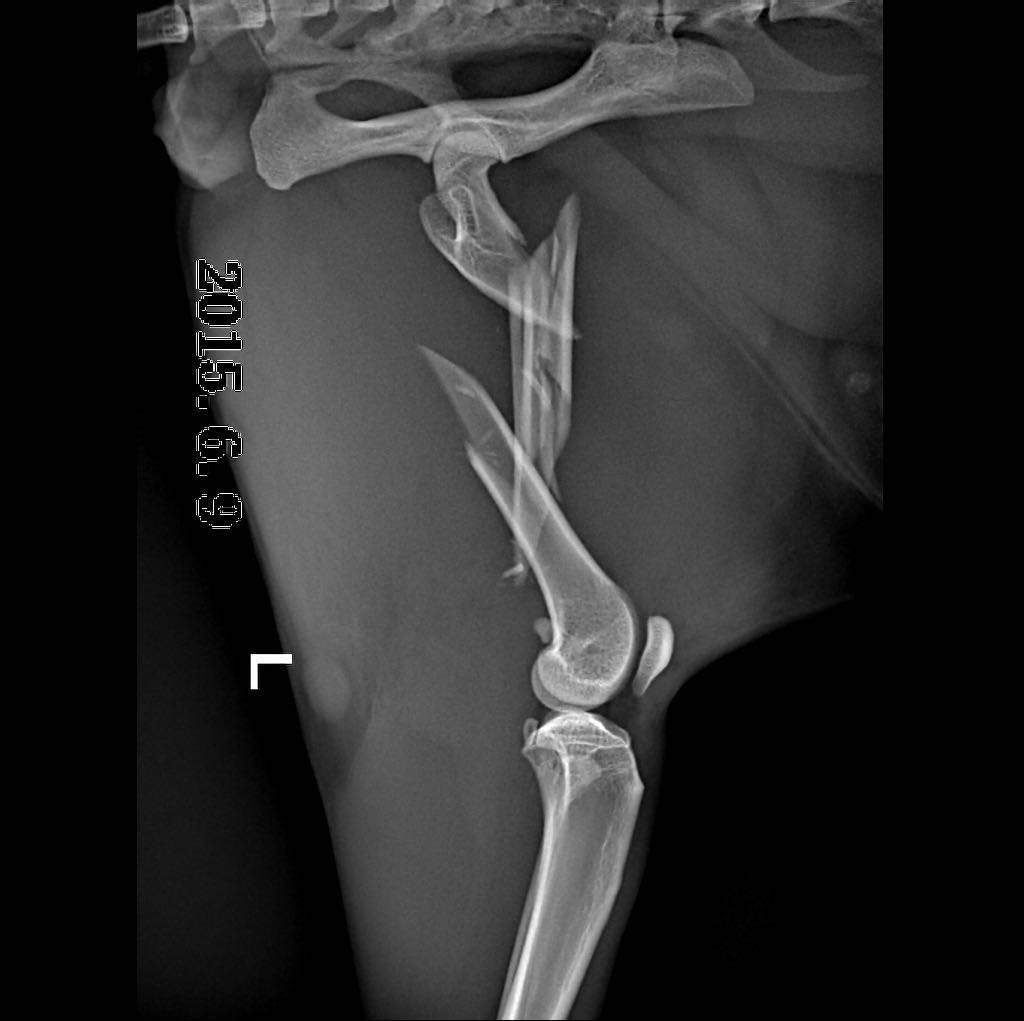

摘 要:动物发生脊椎骨折一般是由大的外力所致:如咬伤、车祸伤或高楼坠伤